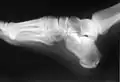

استخوان پاشنه یا کالکانئوس (Calcaneus) بزرگترین استخوان مچ پا است. زردپی آشیل به خلف این استخوان میچسبد.

استخوان پاشنه در قدام با استخوان تاسی (کوبوئید) و در ناحیه فوقانی با استخوان قاپ (تالوس) مفصل میشود.

پای انسان در ناحیه مچ پا شامل هفت استخوان میباشد که بزرگترین آن استخوان پاشنه بوده و بیشترین وزن بدن را نیز تحمل میکند و در بخش ابتدای پا، پیش از قوس آن قرار دارد. ساختارش نسبتاً به شکل مکعب مستطیل است و در اطراف آن بستها (رباطها) و ماهیچههای زیادی واقع شدهاند. چنانچه در این استخوان، یک زائده خرد پدیدار گردد (خار پاشنه) میتواند دردناک شده و نهایتاً راه رفتن را دشوار میسازد.